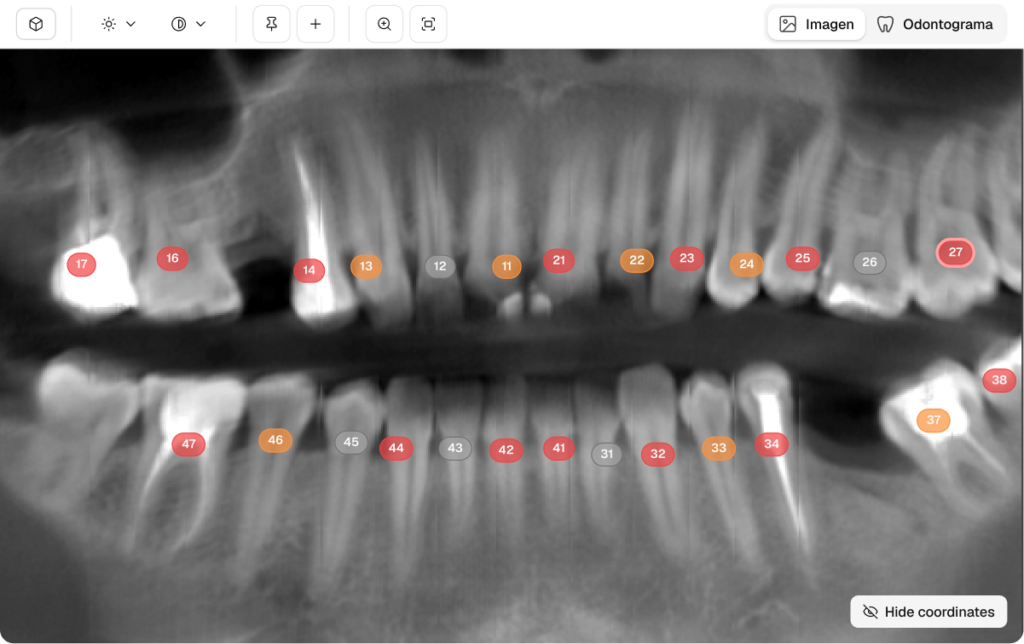

Dentomo se ha entrenado con una amplia base de datos de imágenes de tomografía computarizada de haz cónico (CBCT), lo que le permite ofrecer una precisión sin igual en la identificación y clasificación de más de 10 patologías dentales críticas, además de un análisis exhaustivo de más de 14 tratamientos previos. Nuestra última versión va más allá de la simple detección, ya que introduce un editor con intervención humana y un módulo de estadísticas diseñado para la gestión clínica a escala empresarial. Dentomo ahora ofrece un control de diagnóstico total, lo que permite a los médicos refinar los hallazgos de IA y realizar un seguimiento del rendimiento organizacional con una precisión basada en datos.

Los algoritmos avanzados de Dentomo garantizan una alta precisión en la identificación y clasificación de patologías dentales y tratamientos previos, con una precisión superior al 91 %. Gracias a esta precisión, los odontólogos pueden ofrecer planes de tratamiento más informados y eficaces, lo que se traduce en mejores resultados y una mayor satisfacción de los pacientes.

La capacidad de Dentomo para identificar automáticamente más de 10 patologías bucales y más de 14 tratamientos, ahora con búsqueda detallada por entidad, clínica o usuario ofrece información completa sobre la salud bucal del paciente. Esta gran cantidad de información permite a los profesionales tomar decisiones bien informadas, lo que lleva a planes de tratamiento más personalizados y un mayor nivel de atención médica.